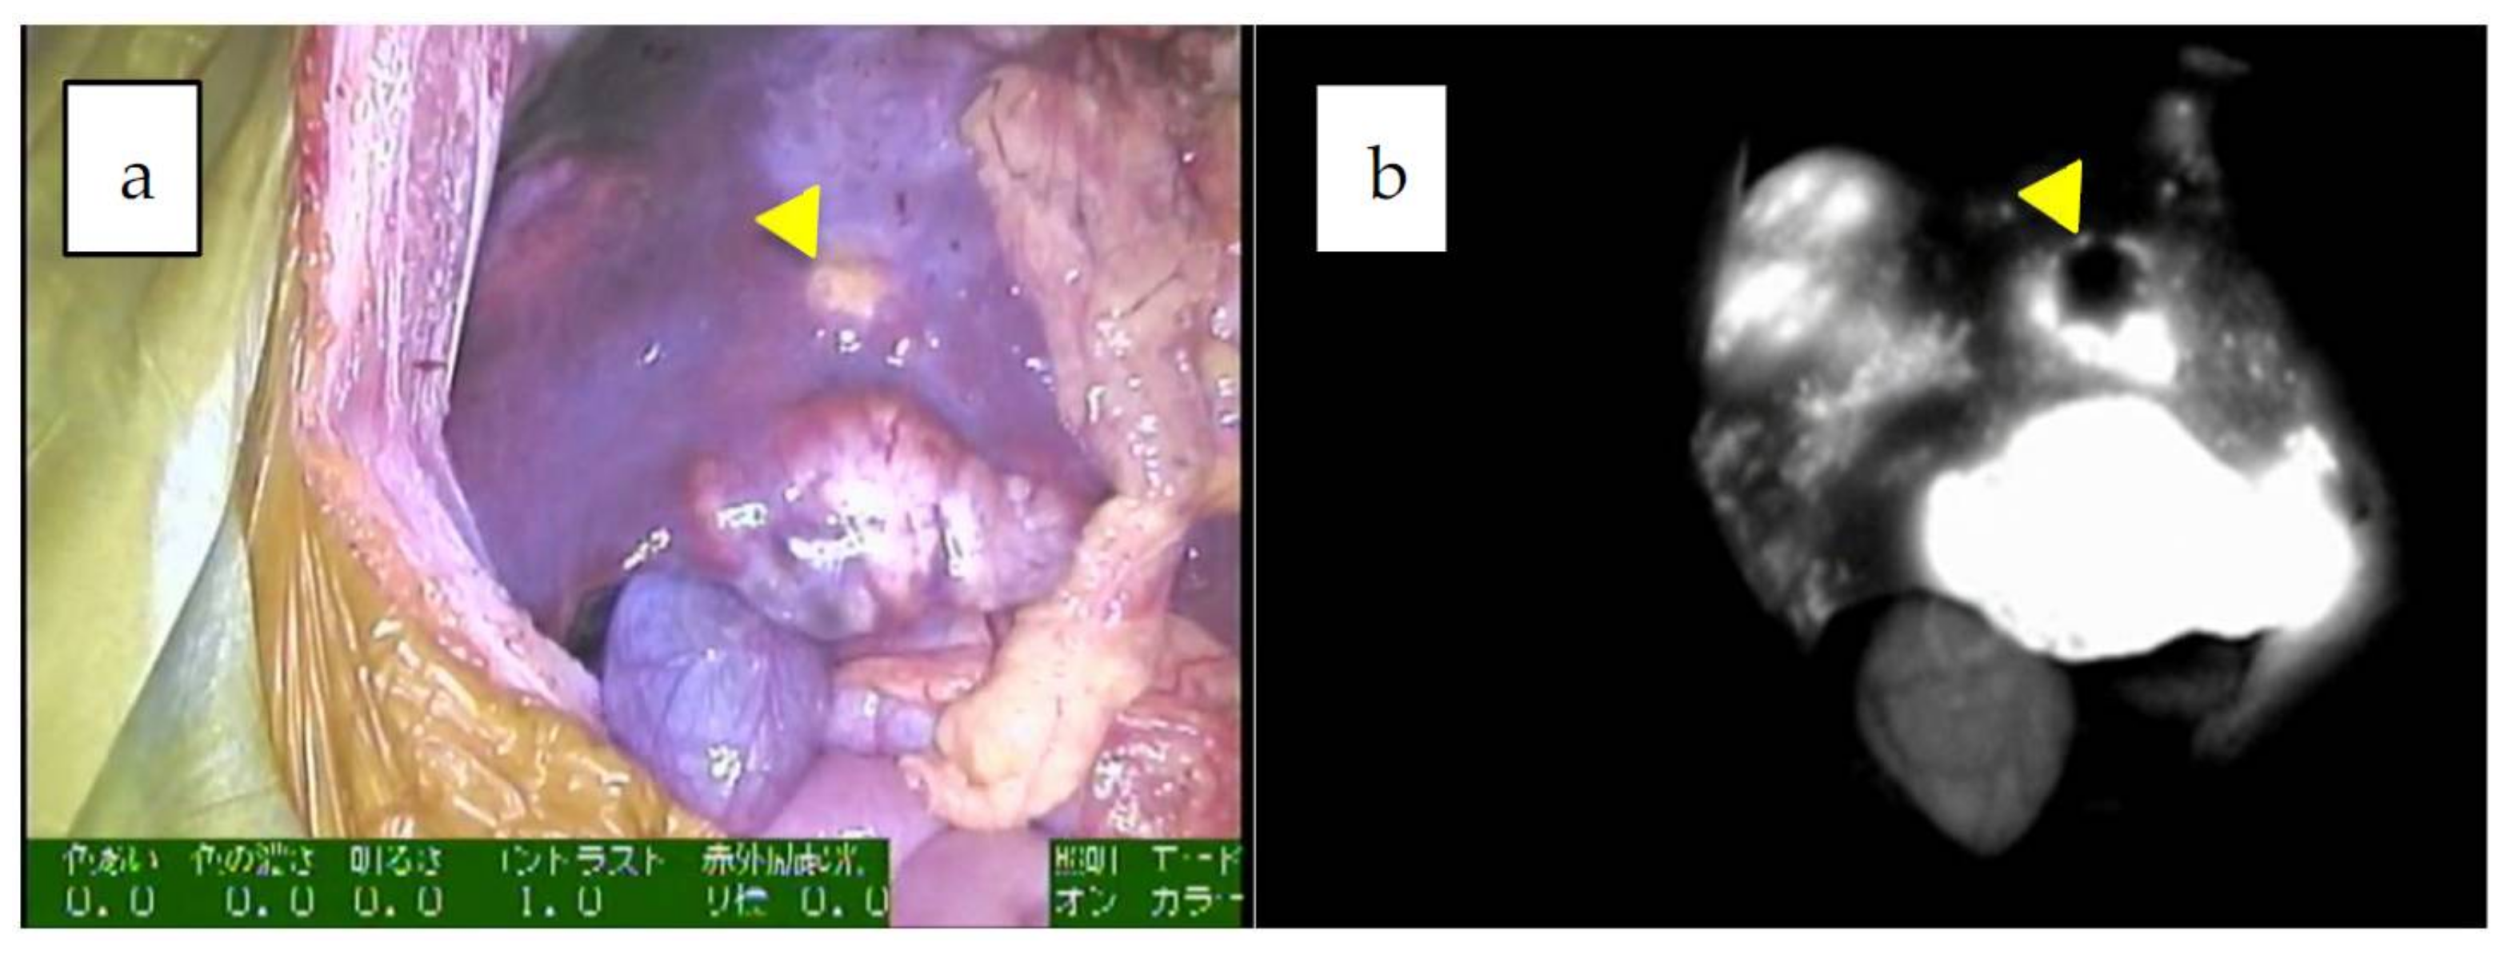

Figure 1.

a,b: Multiple fluorescent spots are observed under near-infrared (NIR) in the liver. Of note, some nodules show a rim-type fluorescence pattern, indicated by an arrowhead (combined fetal and embryonal subtype, post-chemotherapy).